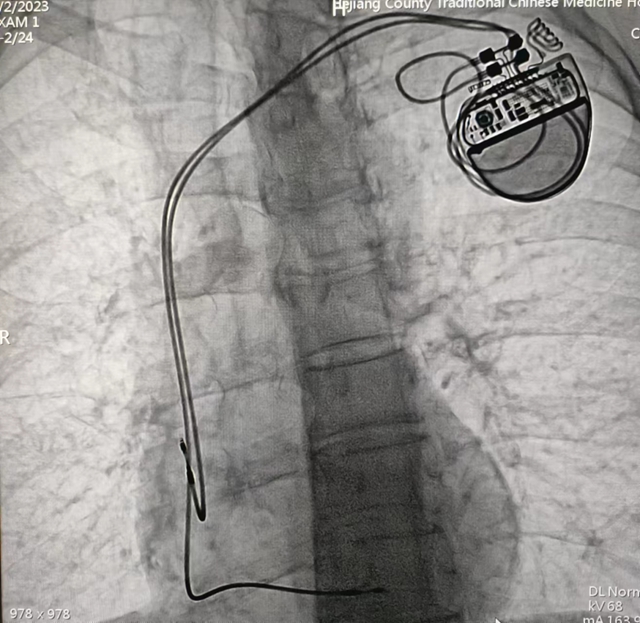

经过充分的术前准备,由心血管内科主任黄胜主刀,在介入医学中心医护团队默契配合下,成功为患者行永久性心脏起搏器植入术。手术历经1小时左右顺利完成,起搏器感知、起搏功能良好,患者生命体征平稳。近日,科室又为两名患者成功开展了此手术。

黄胜介绍,心脏起搏器植入术具有切口小、不开胸、安全系数较高等优势。通过植入心脏起搏器发出的规律脉冲,可以维持心脏的正常跳动和射血功能,最大限度挽救患者生命,大大改善心脏疾病患者的生活质量。

该技术的成功开展,填补了医院在这一技术领域的空白,推动医院心血管内科专业技术再上新台阶,为患者减轻经济负担同时,节约患者急救时间,为县域内心血管疾病患者带来了福音。